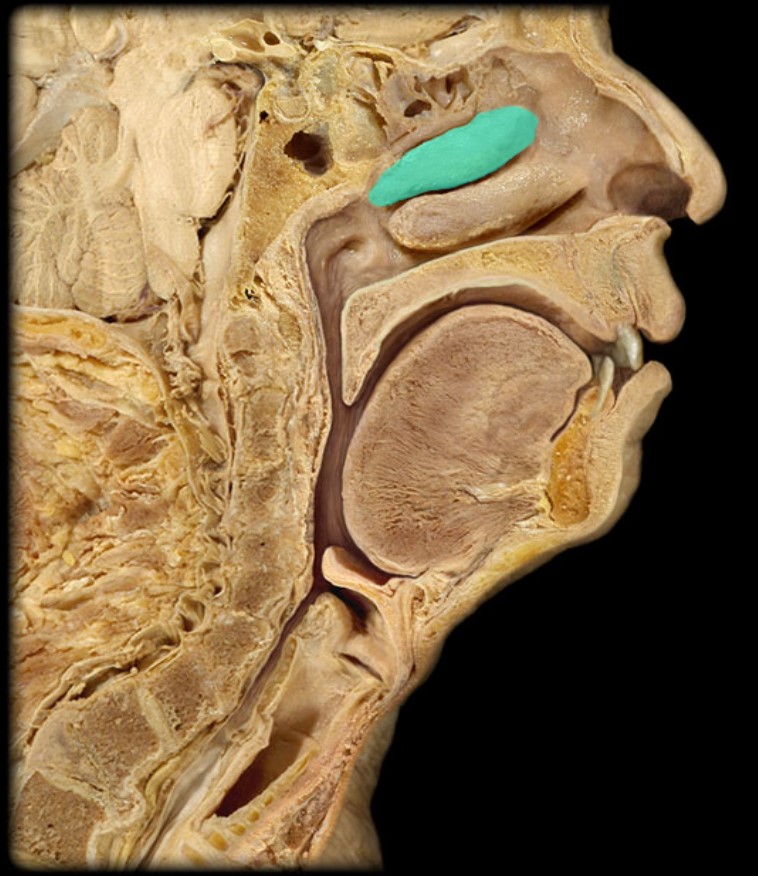

Uvula

Soft Palate

Palatine Bone

Maxilla

Torus Tubarius

Sphenoid Sinus

Inferior Nasal Concha

Middle Nasal Concha

Superior Nasal Concha